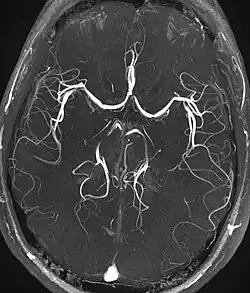

Angiography

Magnetic resonance angiography (MRA) generates pictures of the arteries to evaluate them for stenosis (abnormal narrowing) or aneurysms (vessel wall dilatations, at risk of rupture). MRA is often used to evaluate the arteries of the neck and brain, the thoracic and abdominal aorta, the renal arteries, and the legs (called a "run-off"). A variety of techniques can be used to generate the pictures, such as administration of a paramagnetic contrast agent (gadolinium) or using a technique known as "flow-related enhancement" (e.g., 2D and 3D time-of-flight sequences), where most of the signal on an image is due to blood that recently moved into that plane (see also FLASH MRI).[53]

Techniques involving phase accumulation (known as phase contrast angiography) can also be used to generate flow velocity maps easily and accurately. Magnetic resonance venography (MRV) is a similar procedure that is used to image veins. In this method, the tissue is now excited inferiorly, while the signal is gathered in the plane immediately superior to the excitation plane—thus imaging the venous blood that recently moved from the excited plane.[54]